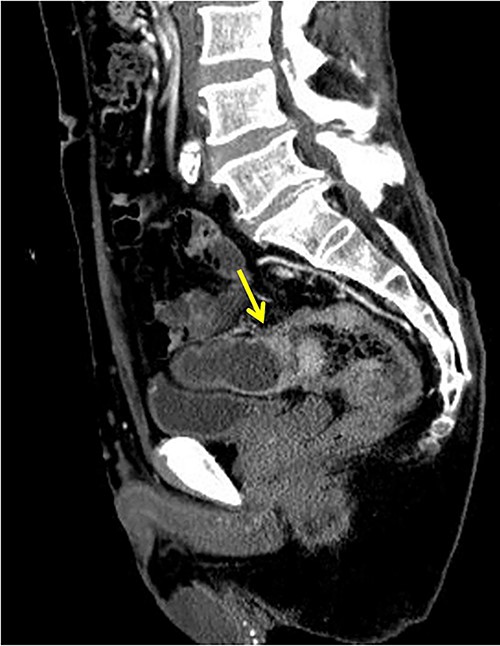

The patient was a 65-year-old man presenting to our hospital with complications of diarrhea for a year and weight loss. Colonoscopy showed rectal cancer on the anal verge (13 cm) with circumferential stenosis. Laboratory findings showed that the serum carcinoembryonic antigen (CEA) level was 4.7 μg/ml and that the serum carbohydrate antigen 19-9 (CA19-9) was 72.2 U/ml. A computed tomography (CT) scan of the abdomen showed thickening of the rectal wall with inflammation. Fistula formation between the ileum and the rectum was observed. Enlarged lymph nodes were also noted around the rectum and no enlarged mesenteric lymph nodes (Fig. 1). The patient was diagnosed with rectal cancer with ileum invasion and then scheduled to undergo surgery. We performed single-incision laparoscopic low anterior resection of the rectum with D3 dissection and partial resection of the ileum. Lymph node dissection, including the area of the inflow vessel, was also performed due to observed lymph node swelling in the mesentery of the ileum around the fistula formation intraoperatively. The operative time was 326 min, and the blood loss volume was 15 ml. Histopathological analysis revealed that the lymph nodes in the small intestine were positive for metastasis, and the diagnosis was pT4b (small intestine) N1 (2/16 (#251, 1/12, #252 1/4, #253 0/0)) M1 (small intestine mesenteric lymph node (1/1)), nonsolid type (por2) adenocarcinoma, ly3, v2 f Stage IV [TNM (tumor, nodes, metastasis) classification] (Fig. 2a and b). After discharge from the hospital, capecitabine plus oxaliplatin was administered for 6 months as adjuvant chemotherapy. The patient has been recurrence-free for 2 years after surgery.

Fistula formation between the small intestine and the rectum was observed. Enlarged lymph nodes were also noted around the rectum.